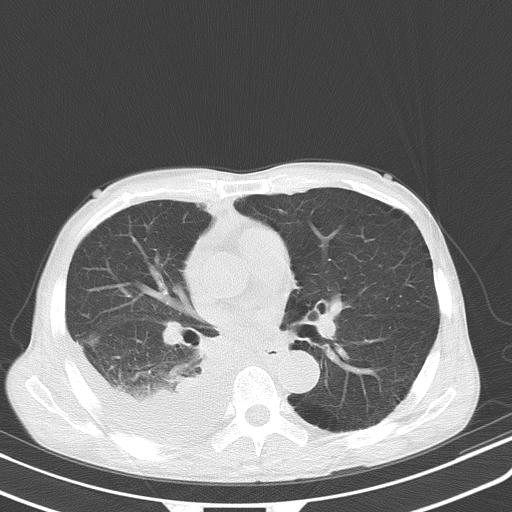

男性 75  咳嗽 一周前发热最高达39

右肺继发型tb并右侧tb性胸腔炎,右侧胸腔大量积液并右下肺膨胀不全,慢支肺气肿、多发肺大泡。建议抽胸水实验室检查并复查排除恶性在占位。

右上肺继发型肺结核,右胸腔中等量积液。

左上肺大泡。

结核的基础上有纵隔淋巴结肿大,右侧有胸水,但右侧纵隔反而窄,说明有肺有不张。

再就是右下肺有块影,和不张混合,还是不能除外肺癌。

1)右肺继发型肺结核。2)左肺胸膜下多发性肺大泡。3)右侧胸腔积液。